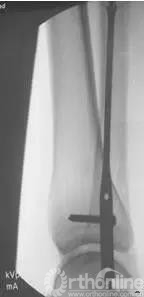

术后侧位片